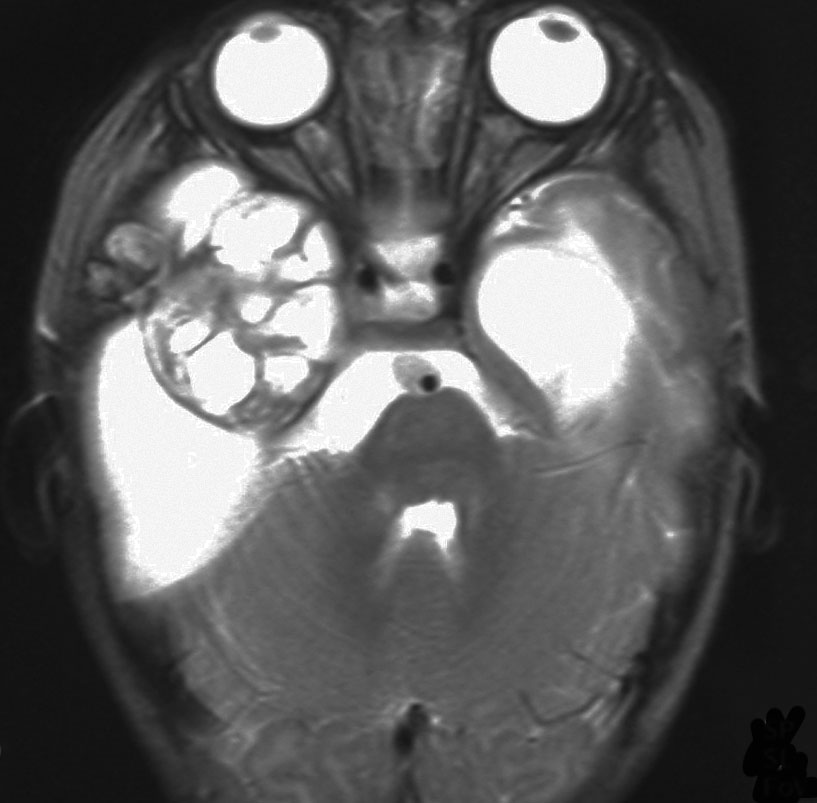

生後5ヶ月の女児に発生した右中頭蓋窩から海綿静脈洞から側頭下窩の成熟奇形腫です。腫瘍のう胞が大きく,右大脳半球の高度の圧排変形がみられます。

のう胞が巨大なので,まずのう胞腹腔シャントをして脳の変形を戻しました。その2ヶ月後に開頭手術で腫瘍を亜全摘出しています。